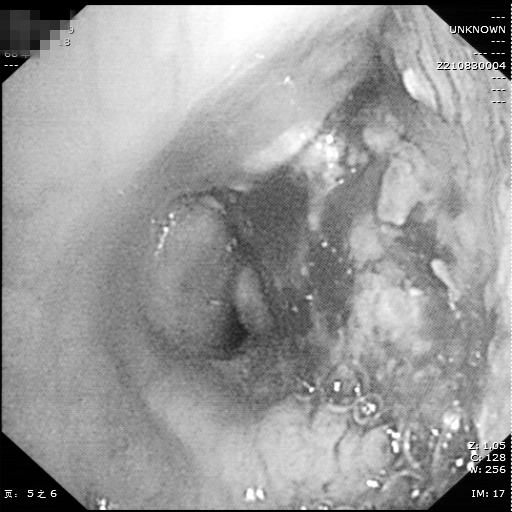

因病因无法明确,且刘大爷一直反复咯血,为求诊治,特地来到湘雅常德医院呼吸内科就诊。入院后,周政副主任医师及李儒鹏副主任医师详细询问病史、仔细查阅外院CT片及支气管镜检查结果后认为:患者胸部CT示纵膈淋巴结明显肿大,可经支气管镜针吸活检明确诊断。与患者及家属商量后,决定为患者行电子支气管镜检查,检查过程中发现右主支气管病变并活动性出血,气管下段黏膜明显隆起,结合胸部CT,两位副主任医师决定为患者进行气管后淋巴结(3P组)经支气管针吸活检术(TBNA)获取淋巴结组织标本。随后,将获取的标本立即制片染色后置于显微镜下观察,立刻送至病理科进行细胞病理学检查,结合右主支气管活检标本病理及免疫组化,最终确诊为:肺鳞癌。

右主支气管病变并出